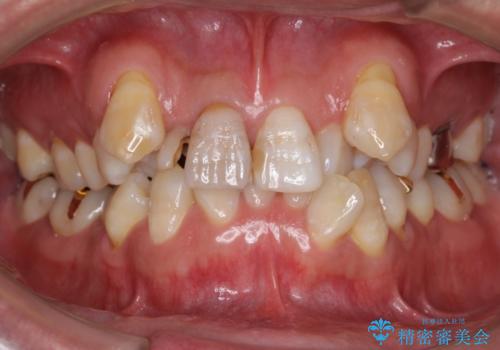

- 神経が死んでいる前歯2本(右上21)をセラミッククラウンでかぶせたいとご希望され、来院された患者様です。

歯並びにより、そのままだときれいに被せ物をいれられない状態でした。

補綴前矯正としてマウスピース矯正(インビザライン)を行った後、セラミッククラウンによる補綴治療を行いました。

重度の叢生(歯並びのがたがた)のため、